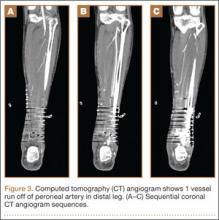

On postoperative day 17, the patient was found to have skin necrosis with exposed hardware over the medial laceration that had resulted from the open fracture (Figure 2). The wound measured 7×6 cm. The plastic surgery team was consulted, and a soft-tissue flap was recommended. Preoperative computed tomography angiogram (Figure 3) revealed 1 vessel runoff in the leg, constituting the peroneal artery, and a conventional angiogram confirmed this finding (Figure 4). Despite these findings, the patient was taken to the operating room 4 weeks after initial injury to try to find a vessel compatible with anastomosis. Intraoperative wound exploration confirmed no patent blood supply for local soft-tissue flap coverage. Therefore, the wound was irrigated and débrided, and a vacuum-assisted closure (VAC) dressing was applied despite exposed hardware and bone. A decision was then made to attempt a cross-leg flap as a salvage procedure, and VAC dressing therapy was continued for several weeks to prepare the recipient site (Figure 5).